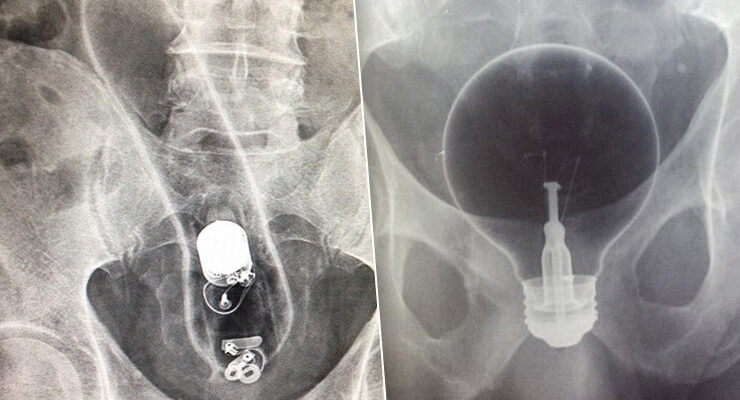

Помнишь старую шутку про лампочку, которую можно засунуть в рот, а вот вытащить — уже нет? Так вот, с некоторыми местами и предметами работает то же правило.